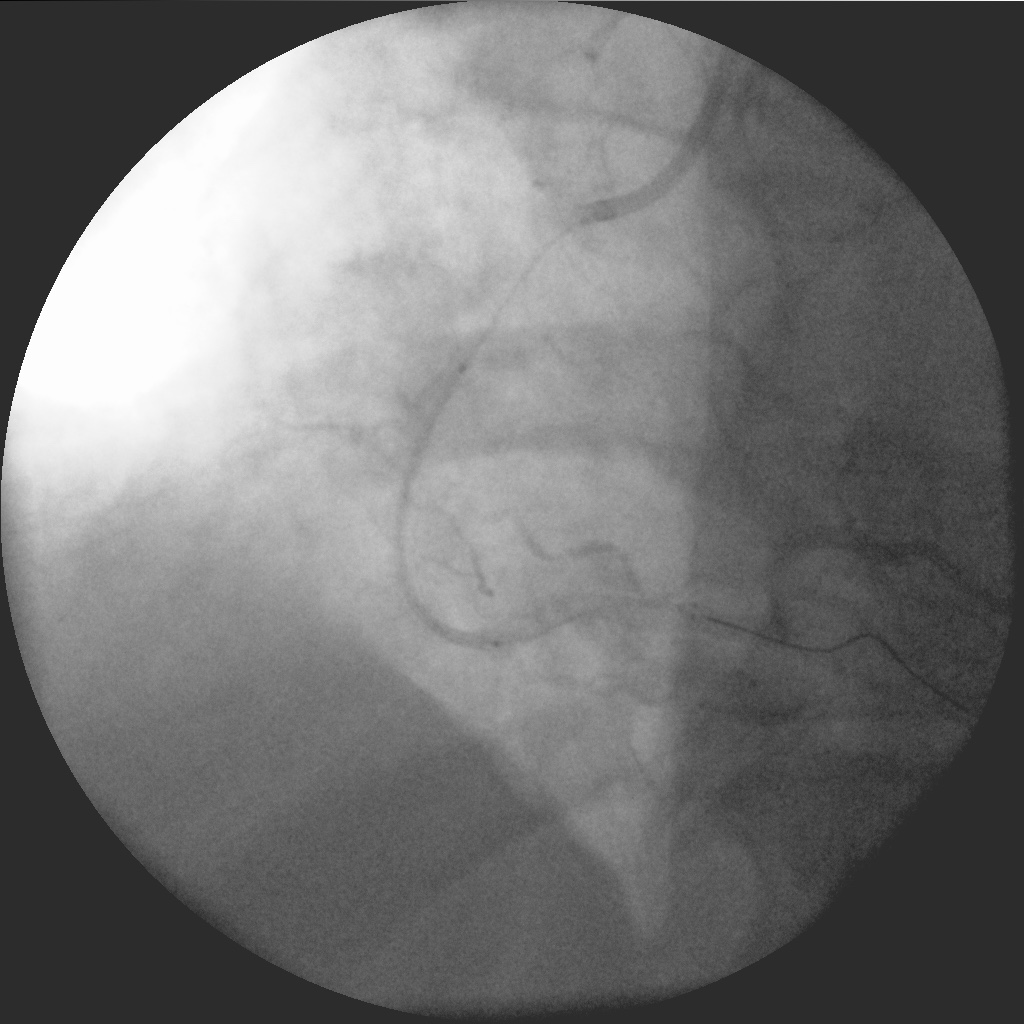

Пациент стентирован ПКА ургентно, ОИМ ЗСЛЖ

Комментарий к файлу: Стеноз ПКА

IM-0001-0020.jpg

На снимке Вы видите уже рестеноз. Пациент обратился в клинику спустя два месяца от момента ургентной установки BMS-стента. Ухудшение состояния отмечал уже спустя месяц, маялся по поликлиникам пока не попал на повторную КВГ.